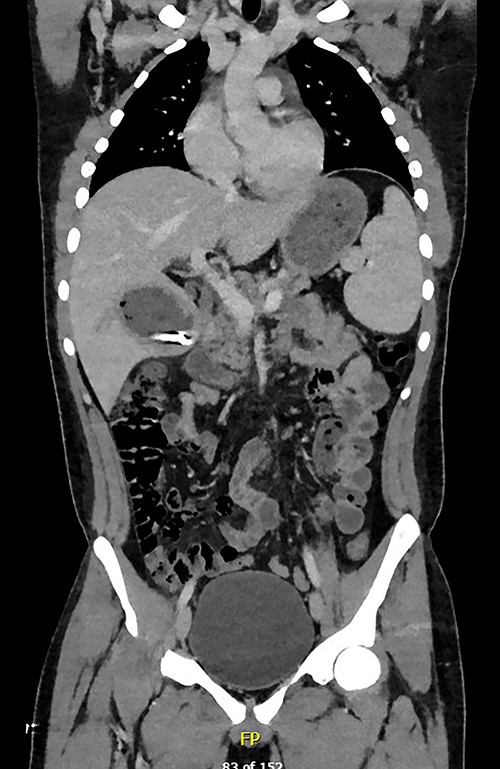

A full lab panel was ordered and revealed a total bilirubin of 1.1, direct bilirubin 0.5, lactate dehydrogenase 196, alkaline phosphatase 80, aspartate transaminase 46 and alanine transaminase 58. A computed tomography (CT) angiographic scan of the chest, abdomen and pelvis revealed the presence of a rim enhancing fluid collection in hepatic segment V with internal gas and containing a metallic foreign body, measuring 8 × 5 cm and consistent with abscess formation (Figs 2–4). The linear tract of the bullet in the right iliac crest was visualized in the CT as well.

Coronal plane of CT showing the retained bullet and hepatic abscess.